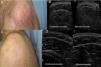

Case 1A 62-year-old man with a personal history of hepatic porphyria cutanea was seen for a lesion covering a large portion of the external aspect of the shoulder and upper left arm. The lesion had appeared 2 months earlier and was occasionally suppurative. The patient had been previously treated for suspected cellulitis with multiple oral antibiotics, without improvement. Physical examination revealed an indurated, erythematous plaque (9×7cm) with poorly defined borders that was hot to the touch (Fig. 1A). Histology revealed non-necrotizing granulomatous dermatitis and the presence of Leishmania bodies within the cytoplasm of the histiocytes. Skin ultrasound (SonoScape, 15-MHz linear probe) was performed to evaluate the extent of the lesion and showed diffuse thickening of the dermis in the affected area (Fig. 1B). Because of the lesion's large size, the patient was treated with intravenous amphotericin B (5mg/kg/d) for 3 days (total dose, 15mg/kg). The lesion resolved in response to treatment (Fig. 1C), as confirmed by subsequent ultrasound (Fig. 1D).

A, Poorly delimited erythematous plaque. B, Ultrasound images showing thickening of the dermis in the affected shoulder, as compared with the unaffected shoulder. C, Resolution of the lesion after treatment. D, Ultrasound images showing the affected and unaffected shoulders after treatment.